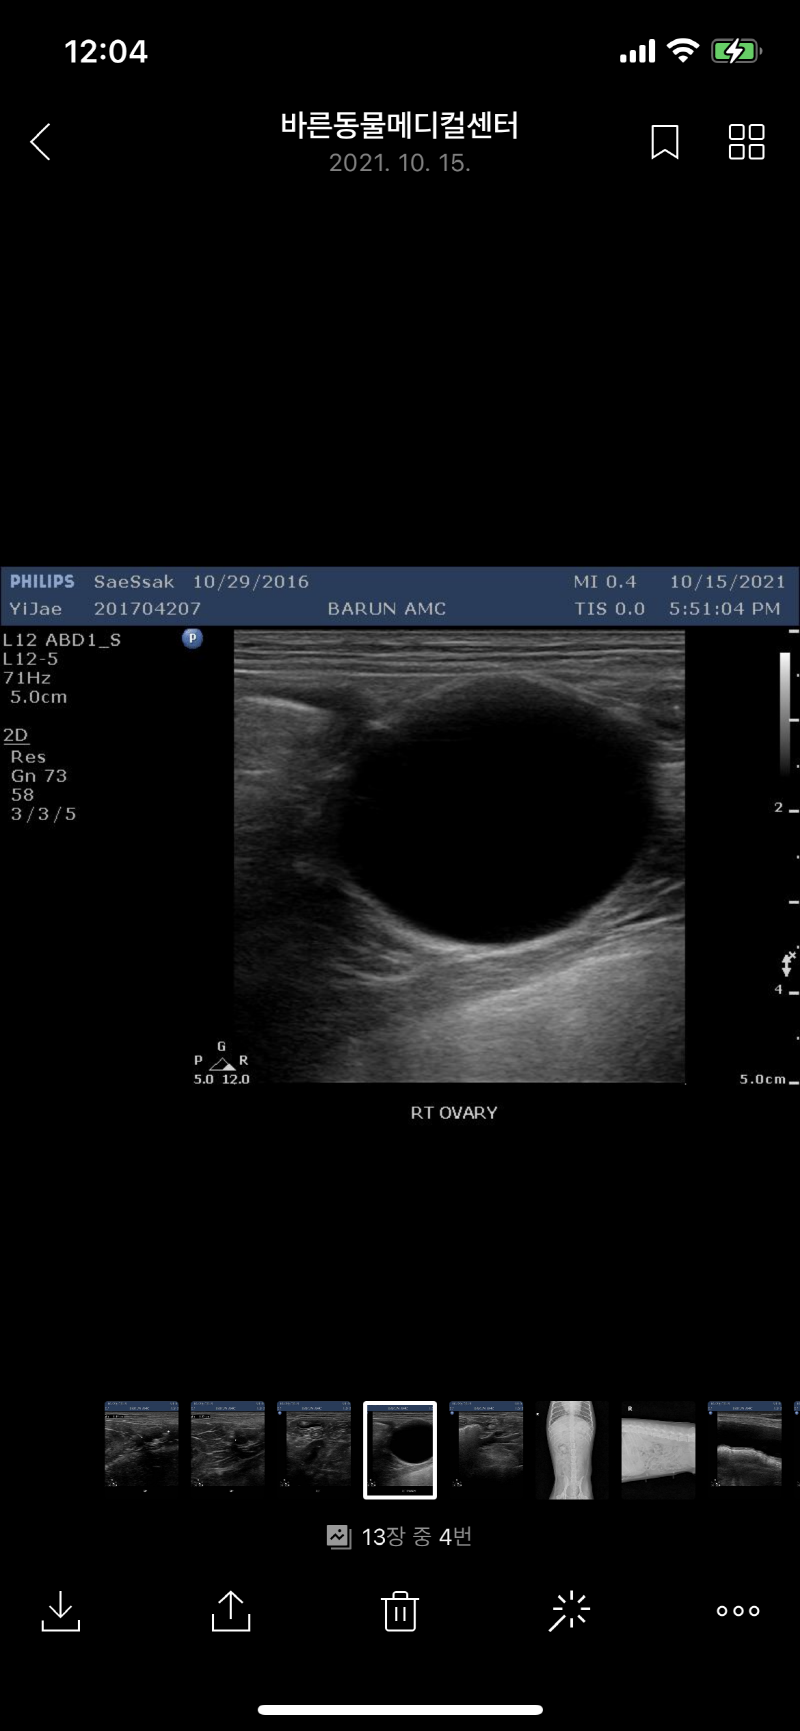

초음파 검사후 난소에 물혹이 발견되다 ㅠㅠ

강아지 초음파 난소 물 혹

최근 건강검진후 발견된 난소에 물혹 ㅠㅠ